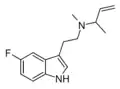

| 5-Fluoro-DMT | artificial | 5-F | CH3 | CH3 | 5-fluoro-N,N-dimethyltryptamine | 22120-36-1 |

| 5-Fluoro-M1MALT | artificial | 5-F | CH3 | CH(CH3)CH=CH2 | 5-fluoro-N-methyl-N-(1-methylallyl)tryptamine | |